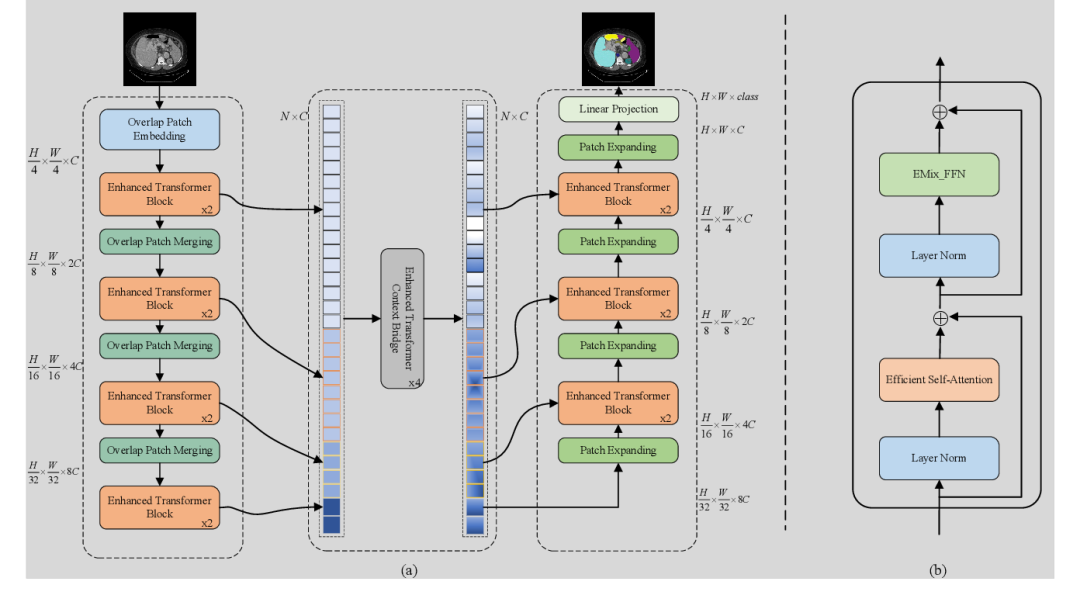

《Mixed Transformer U-Net For Medical Image Segmentation》

《An Effective Medical Image Segmentation Transformer》